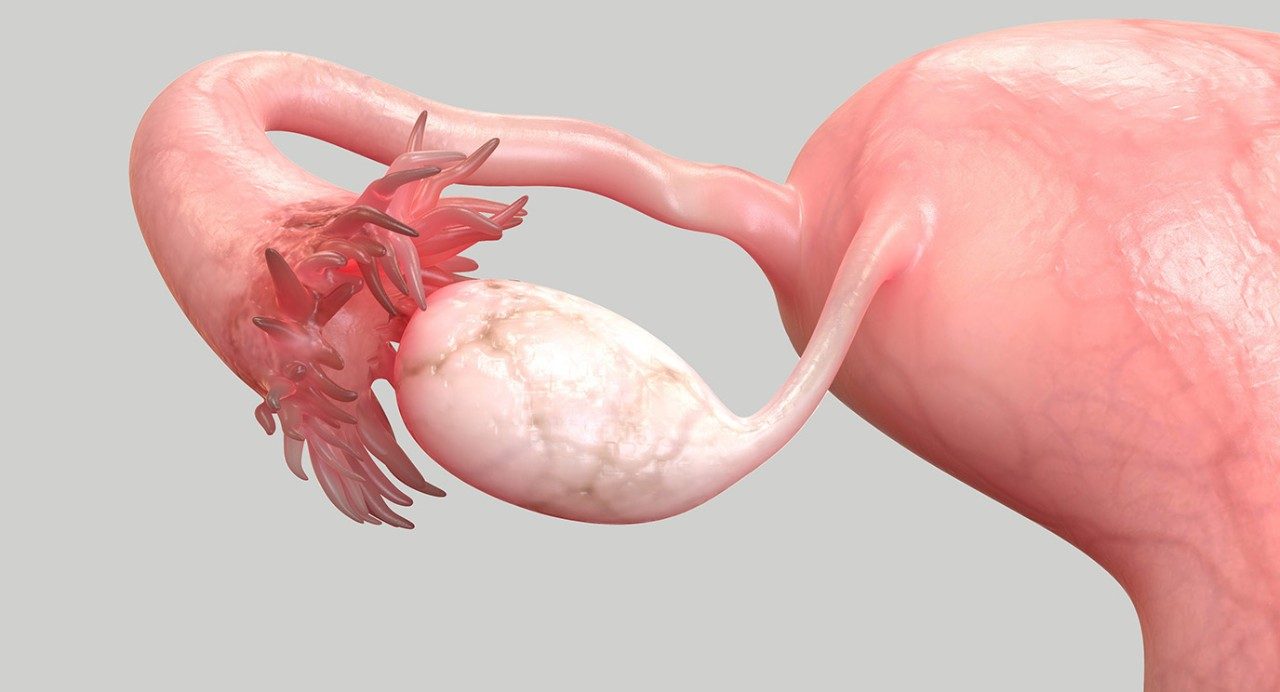

I was on the last day of a bicycling trip in September when I felt a sudden, stabbing pain in my right breast. A biopsy showed the painful lump I found there was actually stage 2, high-grade, triple-positive breast cancer.

After conducting additional tests, Iheme and the rest of my care team — including breast surgical oncologist Dr. Taiwo Adesoye and breast radiation oncologist Dr. Melissa Mitchell — recommended a Phase 2 clinical trial with a novel HER2 targeted therapy drug in combination with endocrine therapy. It involved a new bispecific antibody called zanidatamab that was already being used successfully to treat HER2+ metastatic breast cancer, bile duct cancer and other gastric cancers. The preliminary results of the Phase 2 clinical trial were promising. So, I agreed to take part.

By the time I finished the clinical trial, my breast was totally clear, so I could have a lumpectomy instead of a mastectomy. The pathology report showed I’d had a complete pathological response. There was no evidence of residual cancer in my breast or lymph nodes.